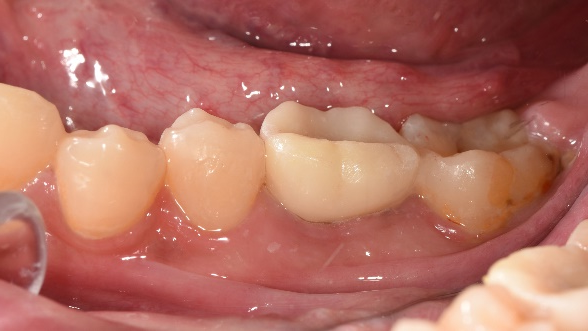

4.裝上假牙,完成治療

治療完成X光片